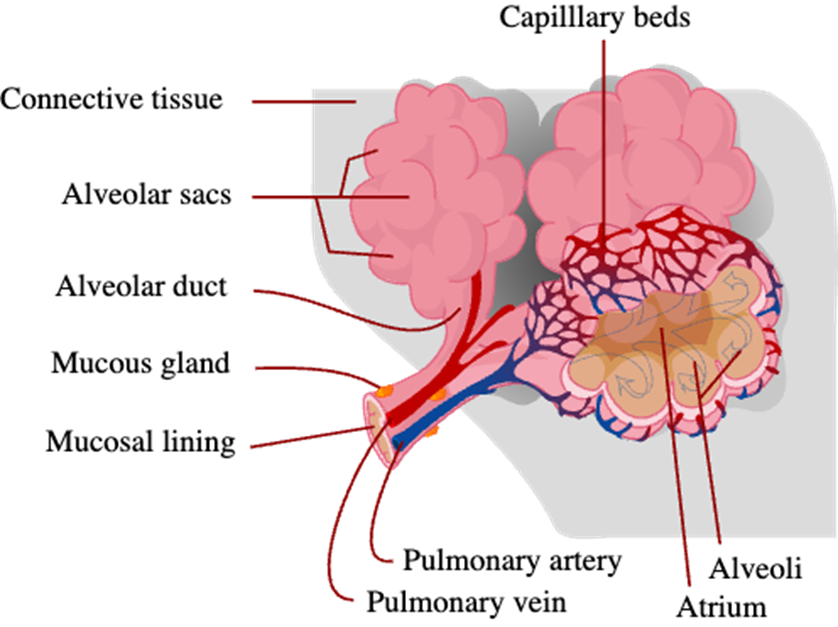

Central Cyanosis Causes

Decreased arterial oxygen saturation:

Impaired pulmonary function

Alveolar hypoventilation

Inhomogeneity in pulmonary ventilation and perfusion

Impaired oxygen diffusion

Anatomic shunts

Congenital heart disease

Pulmonary arteriovenous fistulas

Multiple small intrapulmonary shunts